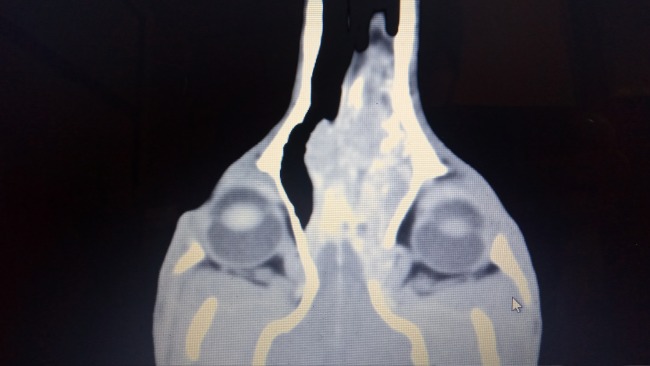

Ogi kichał od początku. Kichał strasznie. Z noska wyciekały mu gluty we wszystkich kolorach - od białych, żółtych, zielonych po brunatne. Aż zaczął kichać krwią. Próbowaliśmy go leczyć antybiotykami, sterydami, robiliśmy posiewy, był na zabiegu rinoskopii, który nic nie wykazał. Zdecydowaliśmy się na tomografię komputerową, która niestety pokazała nam ogromną zmianę. Nowotwór zajmuje prawie całą przestrzeń w nosie, przebija się do mózgu i gałek ocznych. Zniszczył też kość między oczami do tego stopnia, że pojawił się tam odstający guz.